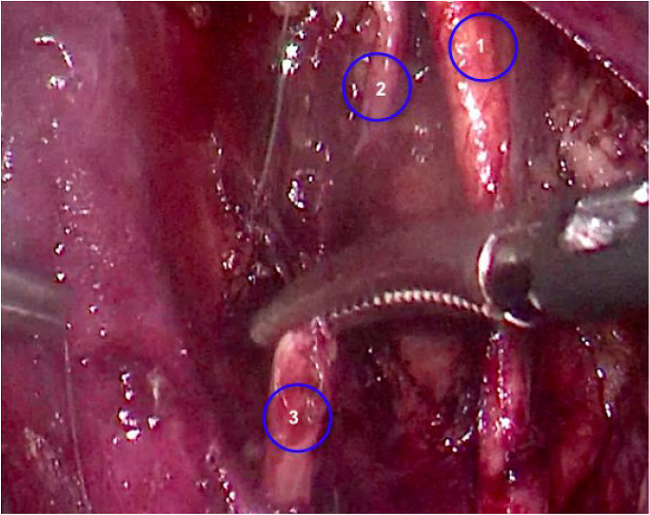

Adicionalmente, durante el procedimiento de disección del paquete ganglionar obturador izquierdo se produce una lesión completa del nervio obturador con energía bipolar avanzada (ligasure ®) que se identifica en el acto operatorio (Figura 1). Se procede a realizar una reconstrucción con neurorrafia primaria término-terminal con sutura no absorbible (prolene 5-0®) y puntos separados (Figura 2) vía laparoscópica. El reporte final de la patología informó carcinoma de células escamosas grandes no queratinizante, ulcerado, infiltrante, 5 x 8 mm de extensión horizontal, sin evidencia de invasión linfovascular, vértice y bordes libres de lesión y 43 ganglios linfáticos pélvicos negativos para compromiso tumoral. En la valoración posoperatoria, el grupo de re- habilitación indica estudios de neuroconducción y electromiografía a los 15 días del procedimiento que confirman lesión del nervio obturador izquierdo tipo axonotmesis con signos de reinervación (Figura 3). Al examen físico presenta clínica de dolor difuso en el muslo izquierdo, en cara anterior y lateral, intensidad 3-4/10 según escala análoga del dolor; en la evaluación de fuerza muscular se observa debilidad de flexores de cadera y aductores de cadera izquierdos (4/5 en la escala de fuerza muscular modificada). Presenta alteración en la velocidad de la marcha sin cambios en su patrón funcional. El estudio de electrofisiología mostró buen pronóstico dado que conservaba potencial de acción motor compuesto, reclutamiento normal y signos de reinervación, condición que orientó la estrategia de rehabilitación para optimizar la estimulación de la fibra muscular con electroterapia, además de la ejecución de ejercicios activos de aductores de cadera izquierda para lograr seguridad en la movilidad.